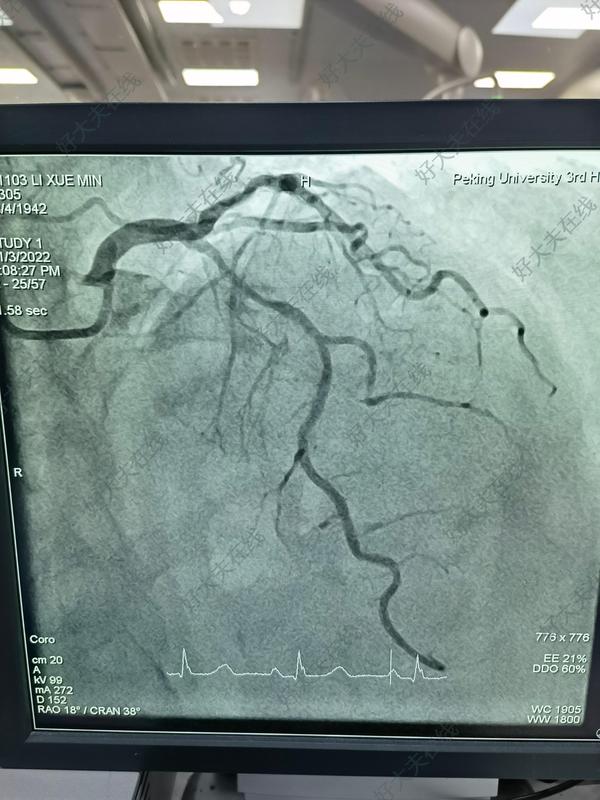

冠脈嚴(yán)重鈣化

冠心病患者什么情況下需要放支架治療?一文讀懂關(guān)鍵指征一、認(rèn)識冠心病與支架治療的本質(zhì)冠心病是由于冠狀動脈粥樣硬化導(dǎo)致血管狹窄、心肌缺血的疾病。當(dāng)血管狹窄到一定程度,藥物無法有效控制癥狀時,支架治療(經(jīng)皮冠狀動脈介入術(shù),PCI)成為重要手段。支架的作用:通過植入金屬或生物可吸收支架,撐開狹窄血管,恢復(fù)心肌供血,緩解胸痛、胸悶等癥狀,降低心肌梗死風(fēng)險。二、需放支架的核心臨床場景(一)急性心肌梗死(心梗)——急診支架的黃金指征-關(guān)鍵機制:冠狀動脈突發(fā)血栓完全堵塞血管,心肌細(xì)胞每分鐘死亡約19億,需爭分奪秒開通血管。-治療原則:發(fā)病12小時內(nèi)(最佳2小時內(nèi))首選急診PCI,通過支架快速恢復(fù)血流,挽救瀕死心肌,降低死亡率。-典型表現(xiàn):突發(fā)劇烈胸痛(壓榨感、瀕死感)、持續(xù)不緩解,伴冷汗、惡心、嘔吐等,需立即撥打120。(二)不穩(wěn)定型心絞痛——預(yù)防心梗的關(guān)鍵節(jié)點-癥狀特點:胸痛發(fā)作頻繁(如靜息時發(fā)作)、持續(xù)時間延長(>20分鐘)、程度加重,含服硝酸甘油效果減弱。-風(fēng)險提示:血管斑塊處于不穩(wěn)定狀態(tài),隨時可能破裂引發(fā)心梗,需通過冠脈造影評估,若狹窄≥75%且藥物控制不佳,需植入支架。(三)穩(wěn)定型心絞痛藥物控制不佳——改善生活質(zhì)量的選擇-判斷標(biāo)準(zhǔn):規(guī)律服用抗心絞痛藥物(如阿司匹林、他汀、β受體阻滯劑等)后,仍頻繁出現(xiàn)胸痛,影響日?;顒樱ㄈ绮叫邪倜?、爬樓梯即誘發(fā)癥狀)。-評估手段:運動負(fù)荷試驗、冠脈CTA或造影顯示血管狹窄≥70%,且病變適合支架植入(如單支或多支血管局限性狹窄)。三、支架治療的評估流程與禁忌(一)嚴(yán)謹(jǐn)?shù)男g(shù)前評估1.?冠脈造影——金標(biāo)準(zhǔn)通過血管內(nèi)成像(如光學(xué)相干斷層成像OCT、血管內(nèi)超聲IVUS)精準(zhǔn)判斷狹窄程度、斑塊性質(zhì)及血管直徑,制定支架型號和植入策略。2.?綜合病情判斷需結(jié)合患者年齡、心功能、合并疾?。ㄈ缣悄虿?、腎功能不全)及病變復(fù)雜性(如左主干病變、彌漫性血管病變)決定。-不適合支架的情況:嚴(yán)重三支血管病變、彌漫性小血管病變、血管扭曲鈣化嚴(yán)重?zé)o法通過導(dǎo)絲等,可能需搭橋手術(shù)(CABG)。(二)禁忌人群-對造影劑過敏且無法替代檢查者;-嚴(yán)重出血傾向(如血小板減少、凝血功能障礙);-晚期腫瘤等預(yù)期壽命有限者;-血管病變過于彌漫或細(xì)?。ㄈ缪苤睆剑?.25mm)。四、支架治療的爭議與科學(xué)認(rèn)知(一)支架不是“萬能藥”,需配合長期管理-術(shù)后誤區(qū):部分患者認(rèn)為“放了支架就根治冠心病”,實則需終身服藥(抗血小板、調(diào)脂、控制血壓血糖等),否則可能出現(xiàn)支架內(nèi)再狹窄或新病變。-健康生活方式:戒煙限酒、低鹽低脂飲食、規(guī)律運動(如每周150分鐘中等強度有氧運動)、控制體重、心理平衡。(二)避免過度醫(yī)療:并非所有狹窄都需支架-臨界病變(狹窄50%-70%):需通過血流儲備分?jǐn)?shù)(FFR)評估是否存在心肌缺血,若缺血證據(jù)不足,優(yōu)先藥物治療+生活方式干預(yù)。-無癥狀輕度狹窄(<50%):診斷為冠狀動脈粥樣硬化,無需支架,重點控制危險因素(如高血壓、高血脂、糖尿?。?。五、術(shù)后管理與長期隨訪(一)術(shù)后即刻注意事項-穿刺部位(手腕或大腿)壓迫止血,避免劇烈活動;-監(jiān)測心率、血壓,觀察有無胸痛復(fù)發(fā)、呼吸困難等;-術(shù)后24小時內(nèi)復(fù)查心電圖、心肌酶,評估手術(shù)效果。(二)長期用藥重點1.?抗血小板治療-雙聯(lián)抗血小板(阿司匹林+替格瑞洛/氯吡格雷)至少1年,預(yù)防支架內(nèi)血栓;-1年后根據(jù)病情調(diào)整為單藥抗血小板治療。2.?他汀類藥物終身服用,目標(biāo)將低密度脂蛋白膽固醇(LDL-C)控制在1.8mmol/L以下,穩(wěn)定斑塊、延緩動脈粥樣硬化進(jìn)展。(三)定期隨訪項目-術(shù)后1個月、3個月、6個月、1年門診復(fù)查,之后每年1次;-復(fù)查項目:血常規(guī)、肝腎功能、血脂、心電圖,必要時行冠脈CTA或造影。六、總結(jié):科學(xué)決策,權(quán)衡獲益與風(fēng)險支架治療是冠心病救治的重要技術(shù),但需嚴(yán)格把握適應(yīng)證?;颊邞?yīng)信任專業(yè)醫(yī)生的評估,結(jié)合自身癥狀、病變程度及全身狀況選擇治療方案。記住:預(yù)防永遠(yuǎn)大于治療,控制三高、健康生活是遠(yuǎn)離支架的第一道防線。如有胸痛不適,務(wù)必及時就醫(yī),避免錯過最佳治療時機。(本科普文章由石家莊市第三醫(yī)院心血管內(nèi)科張國瑞副主任醫(yī)師創(chuàng)作,內(nèi)容僅供科普參考,若有不適癥狀請及時就醫(yī),具體診療請遵醫(yī)囑。)